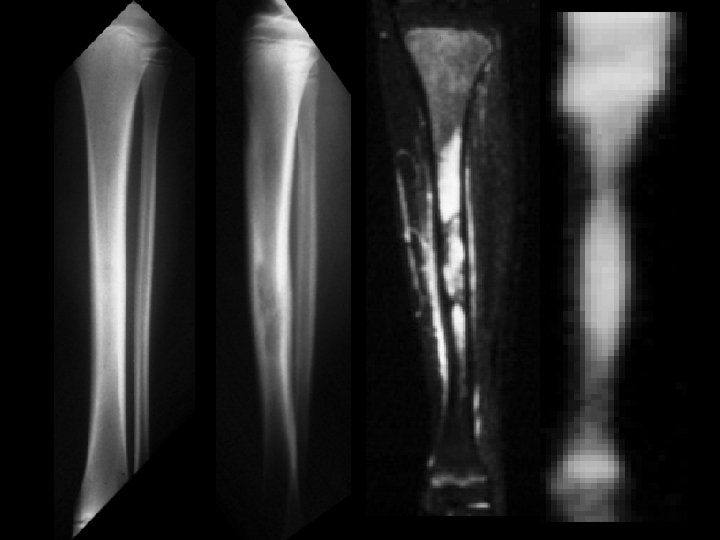

Ewing’s sarcoma • Findings: – Permeative diaphyseal lesion with intense periosteal reaction and soft tissue swelling • ddx: – Osteomyelitis – Langerhan’s cell histiocytosis – Lymphoma